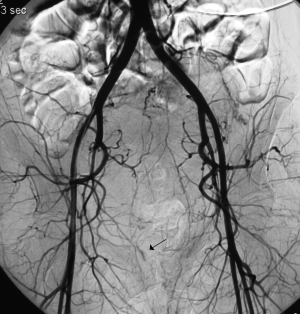

Nechirurgická devaskularizace dělohy

1b971a9fddb79903.PK_1_1

1be2cf1ebf5721ef.obr_1_1